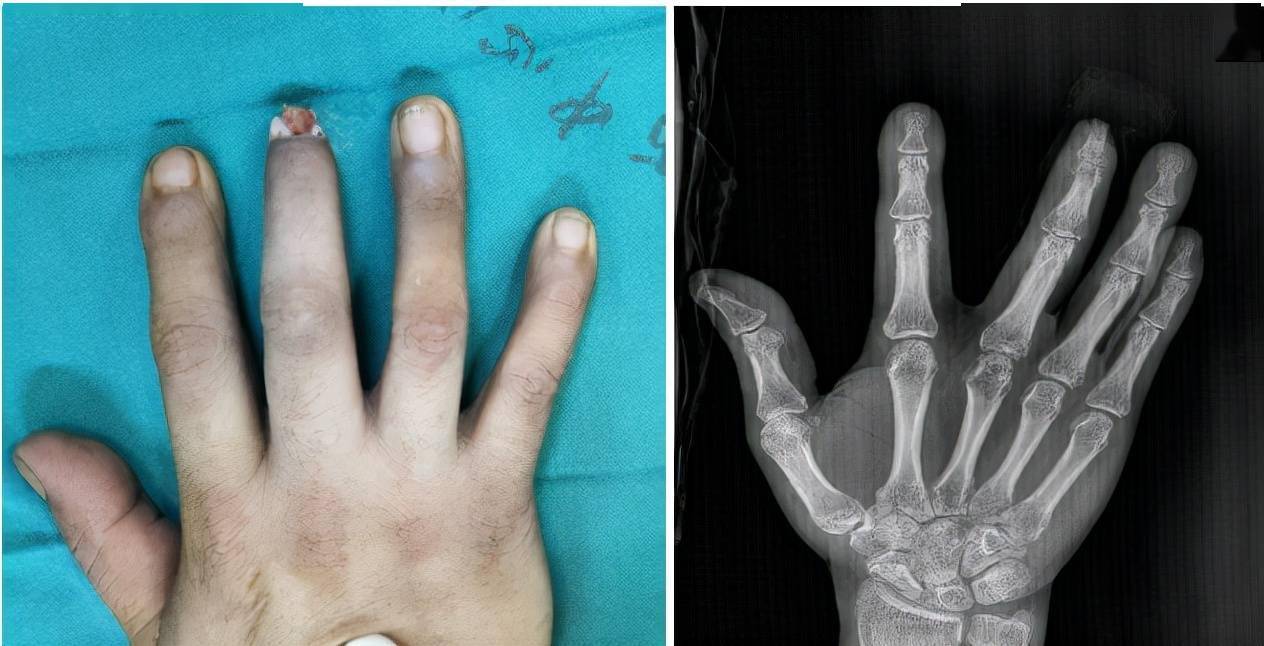

甲下外生性骨疣

整形显微001 在手指头上钉纽扣 骨性锤状指的经典手术治疗 郑元波副主任医师 爱问医生